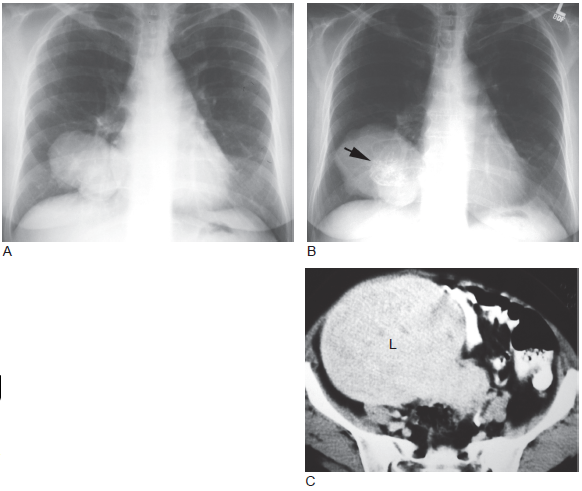

肺肿瘤x光片图,肺肿瘤CT图片

(图) 右肺肉瘤

肺肿瘤CT图片

肺肿瘤和肺癌的图片

肺肿瘤图片

肺肿瘤图片真实